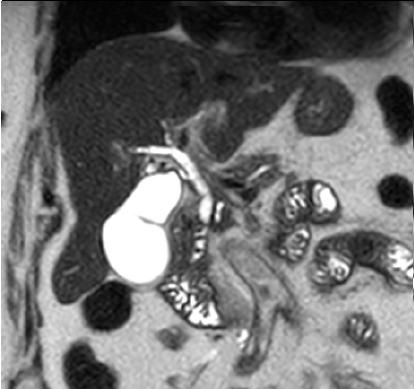

Aspect radiologique d'une

calcul choledocienne .Image de cible du calcul avec

central hyperdensite et a contour de faible de

densite . Image TDM en coupe axiale |

|

Aspect de cible d'une calcul

choledocienne ( fleche rouge ) . Portion dilate en

amont du canal choledoque peut envoyant bien sur ce

coupe . |